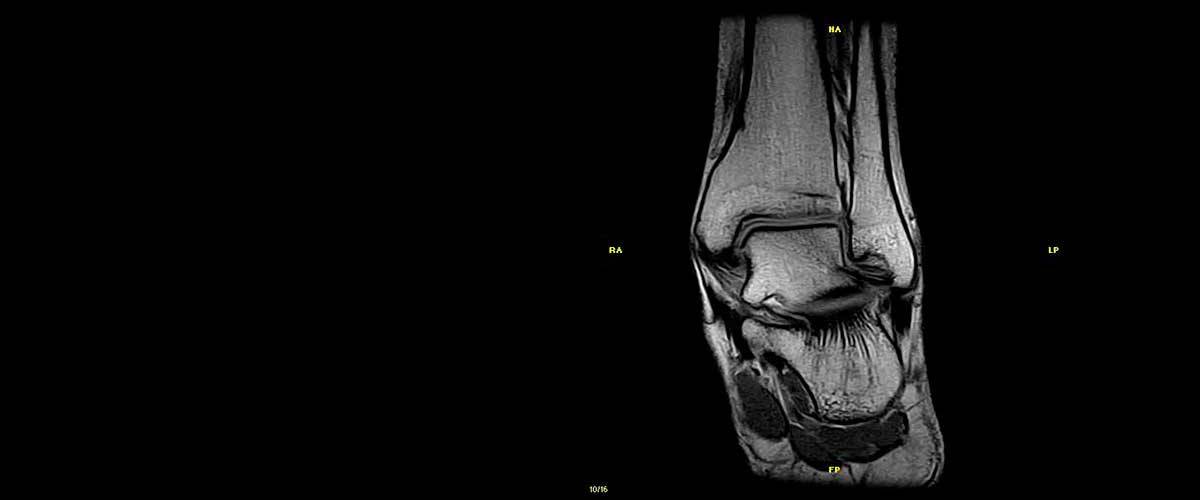

Contamos con equipos de resonancia magnética musculo-esquelética capaces de realizar exámenes con descarga de peso o bipedestación.

En nuestros centros se realizan estudios y diagnósticos de resonancia magnética musculo-esquelética

de Resonancia ,Magnética Musculo-Esquelética, de la marca italiana Esaote, es único en su diseño ya que nos permite realizar exámenes en bipedestación (el paciente estará de pie, para que se tenga otra perspectiva del comportamiento del cuerpo durante el examen).